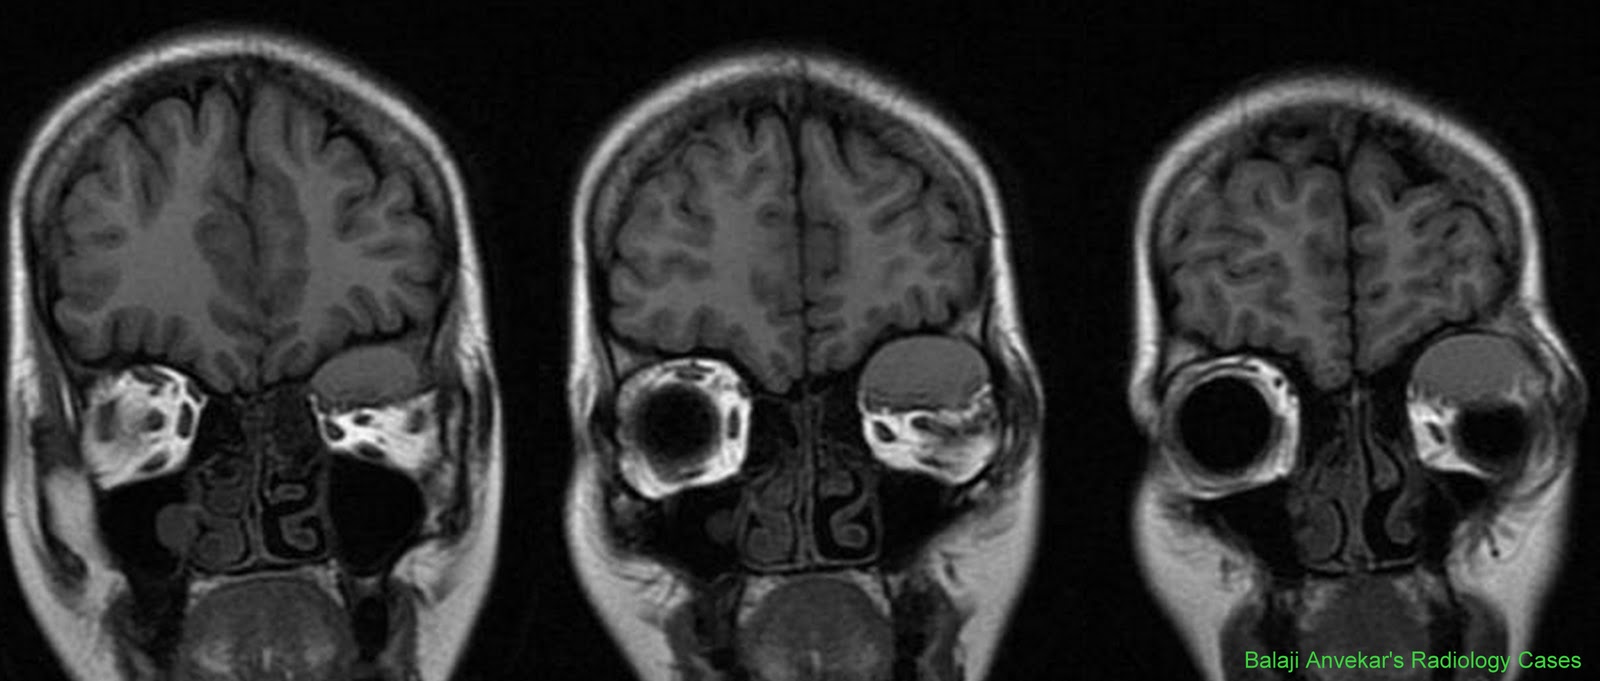

Где сделать кт глаз 111 фото